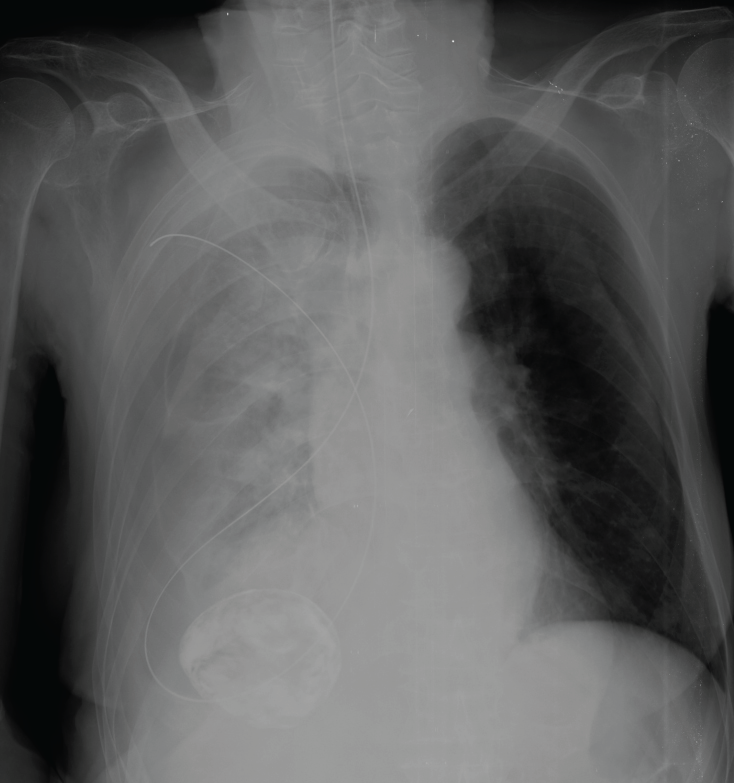

Nasogastric Tube X Ray Nasogastric Tube Problems A feeding tube is a flexible plastic tube placed into your stomach or bowel to help you get nutrition. A nasogastric tube (ng tube) is a thin, flexible plastic tube that’s used for temporary medical purposes. A nasogastric (ng) tube is a feeding tube inserted through your child's nostril. A nasogastric tube (ng tube) can be used for feedings when. Nasogastric Tube Problems.

Misplaced nasogastric tube Image Nasogastric Tube Problems What is a nasogastric tube? Enteric tubes that will be removed within a short period of time can also be passed through the mouth (orogastric). What is a feeding tube? A nasogastric tube (ng tube) can be used for feedings when your child is not able to eat or drink enough by mouth. The most common complications related to the. Nasogastric Tube Problems.